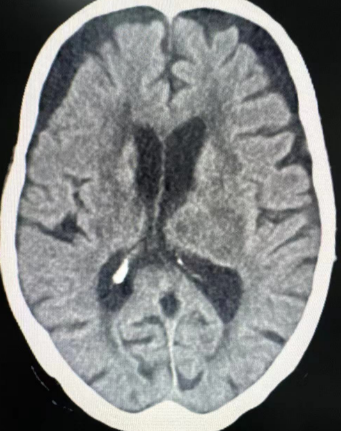

83岁的白奶奶突发意识不清状况,情况危急,随即由120紧急送至陕西冶金医院急诊医学科。头颅CT扫描显示:左侧丘脑、基底节区及侧脑室旁出现急性脑出血,且已破入脑室系统,情况危急。

在完善相关术前检查并获得家属同意后,老人从急诊医学科被送入手术室,神经外科团队立即对患者实施“脑室穿刺引流术”。经过一小时的紧张手术,手术顺利完成,患者转危为安。为老人的康复之路迈出了关键的第一步。

术后,患者被送入重症医学科,在重症医学科医护人员的精心治疗和护理下,目前白奶奶虽遗留右侧肢体活动障碍,但已逐渐开始加强康复功能训练,其上肢肌力为1级,下肢肌力达到2级。